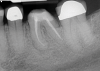

(10.) Tooth No. 31 in this 14-year-old patient does not exhibit caries. It is a “ghost tooth.” The lack of a periapical pathosis, the location of the tooth relative to the inferior alveolar nerve, and the development of tooth No. 32 are all visible in the CBCT image. These factors will aid the clinicians in developing a treatment plan to deal with this unusual internal resorption case.

Figure 10

Identifying the shape and location of the roots of teeth to be removed is critical to performing safe exodontia. Some clinicians virtually deconstruct teeth using CBCT images prior to actually sectioning and removing them. Being able to recognize pathoses and differentiate affected structures from normal structures is key in deciding what the treatment should be and when that treatment should be initiated (Figure 8 through Figure 10). The arena of the oral surgeon is larger than that of many general practitioners, involving the sinuses and condyles and other considerations in and around the entire mandible and maxilla. Certain fractures and other conditions that some general practitioners feel uncomfortable treating are often referred for evaluation and treatment by an oral surgeon. Because of this, oral surgeons require the most accurate and complete diagnostic information available. The American Academy of Oral and Maxillofacial Radiology recommends that "cross-sectional imaging be used for the assessment of all dental implant sites" and has stated that "CBCT is the imaging method of choice for gaining this information."18